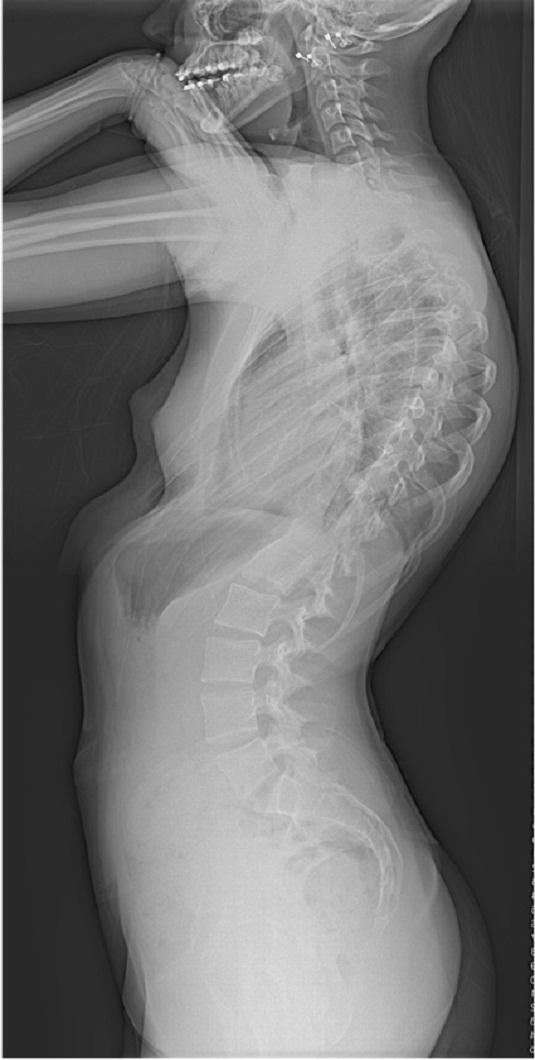

14 year old high school girl noticed gradual hunching over of her back. this spinal curve grew rapidly at the time of growth spurt at puberty for which she sought consultation.

On Clinical and radiological examination, she was diagnosed to have Adolescent Idiopathic Scoliosis with a double thoracic curve of 50 and 46 degree.